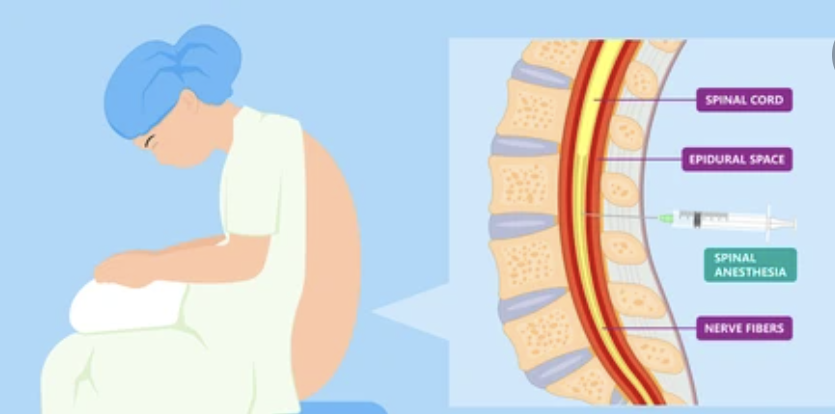

What type of Anaesthesia is given?

Robotic Hip replacement surgery usually takes 45 minutes. So, a spinal anaesthesia is enough. The anaesthetist will give an injection in the lower back which is a very fine prick and numbs the leg for around 3 hours. Occasionally, if there is a cardiac history or stiff/ fused spine, a general anaesthesia is preferred.